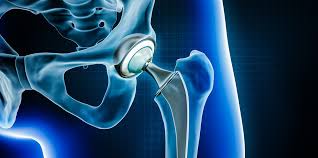

Introduction Hip pain and stiffness can significantly affect mobility and quality of life. Conditions such as osteoarthritis, rheumatoid arthritis, hip fractures, and degenerative joint diseases often lead to chronic...

Introduction Chronic hip pain can make even the simplest activities like walking, sitting, or bending extremely difficult. Over time, conditions such as arthritis or joint damage can severely impact...